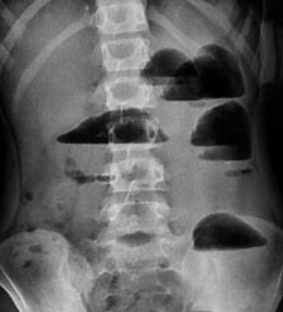

經過放射線檢查診斷就更明確了,其實腸管已經輕度擴張了,而且能看到液氣平面,這種專業術語對普通人可能並不太理解,但是對醫生來說這種現象就已經很明確了,這是一個腸梗阻啊。